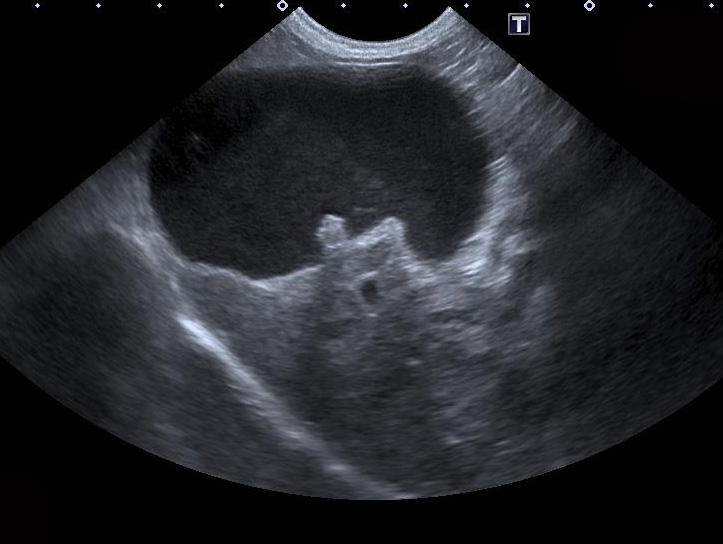

Bien plus que les sapins qui poussent à droite et gauche ou les chansons de Noël en boucle dans les haut-parleurs «haut de gamme» des pharmacies, ce sont nos patients qui nous rappellent un peu plus chaque jour que l’hiver approche… La preuve ? Cette image de vésicule biliaire envoyée par le Dr Guy Beauregard de l’Hôpital vétérinaire Rive-sud.

Voyez-vous la petite maison dans la prairie ?

Ou la grosse maison sous la neige ?